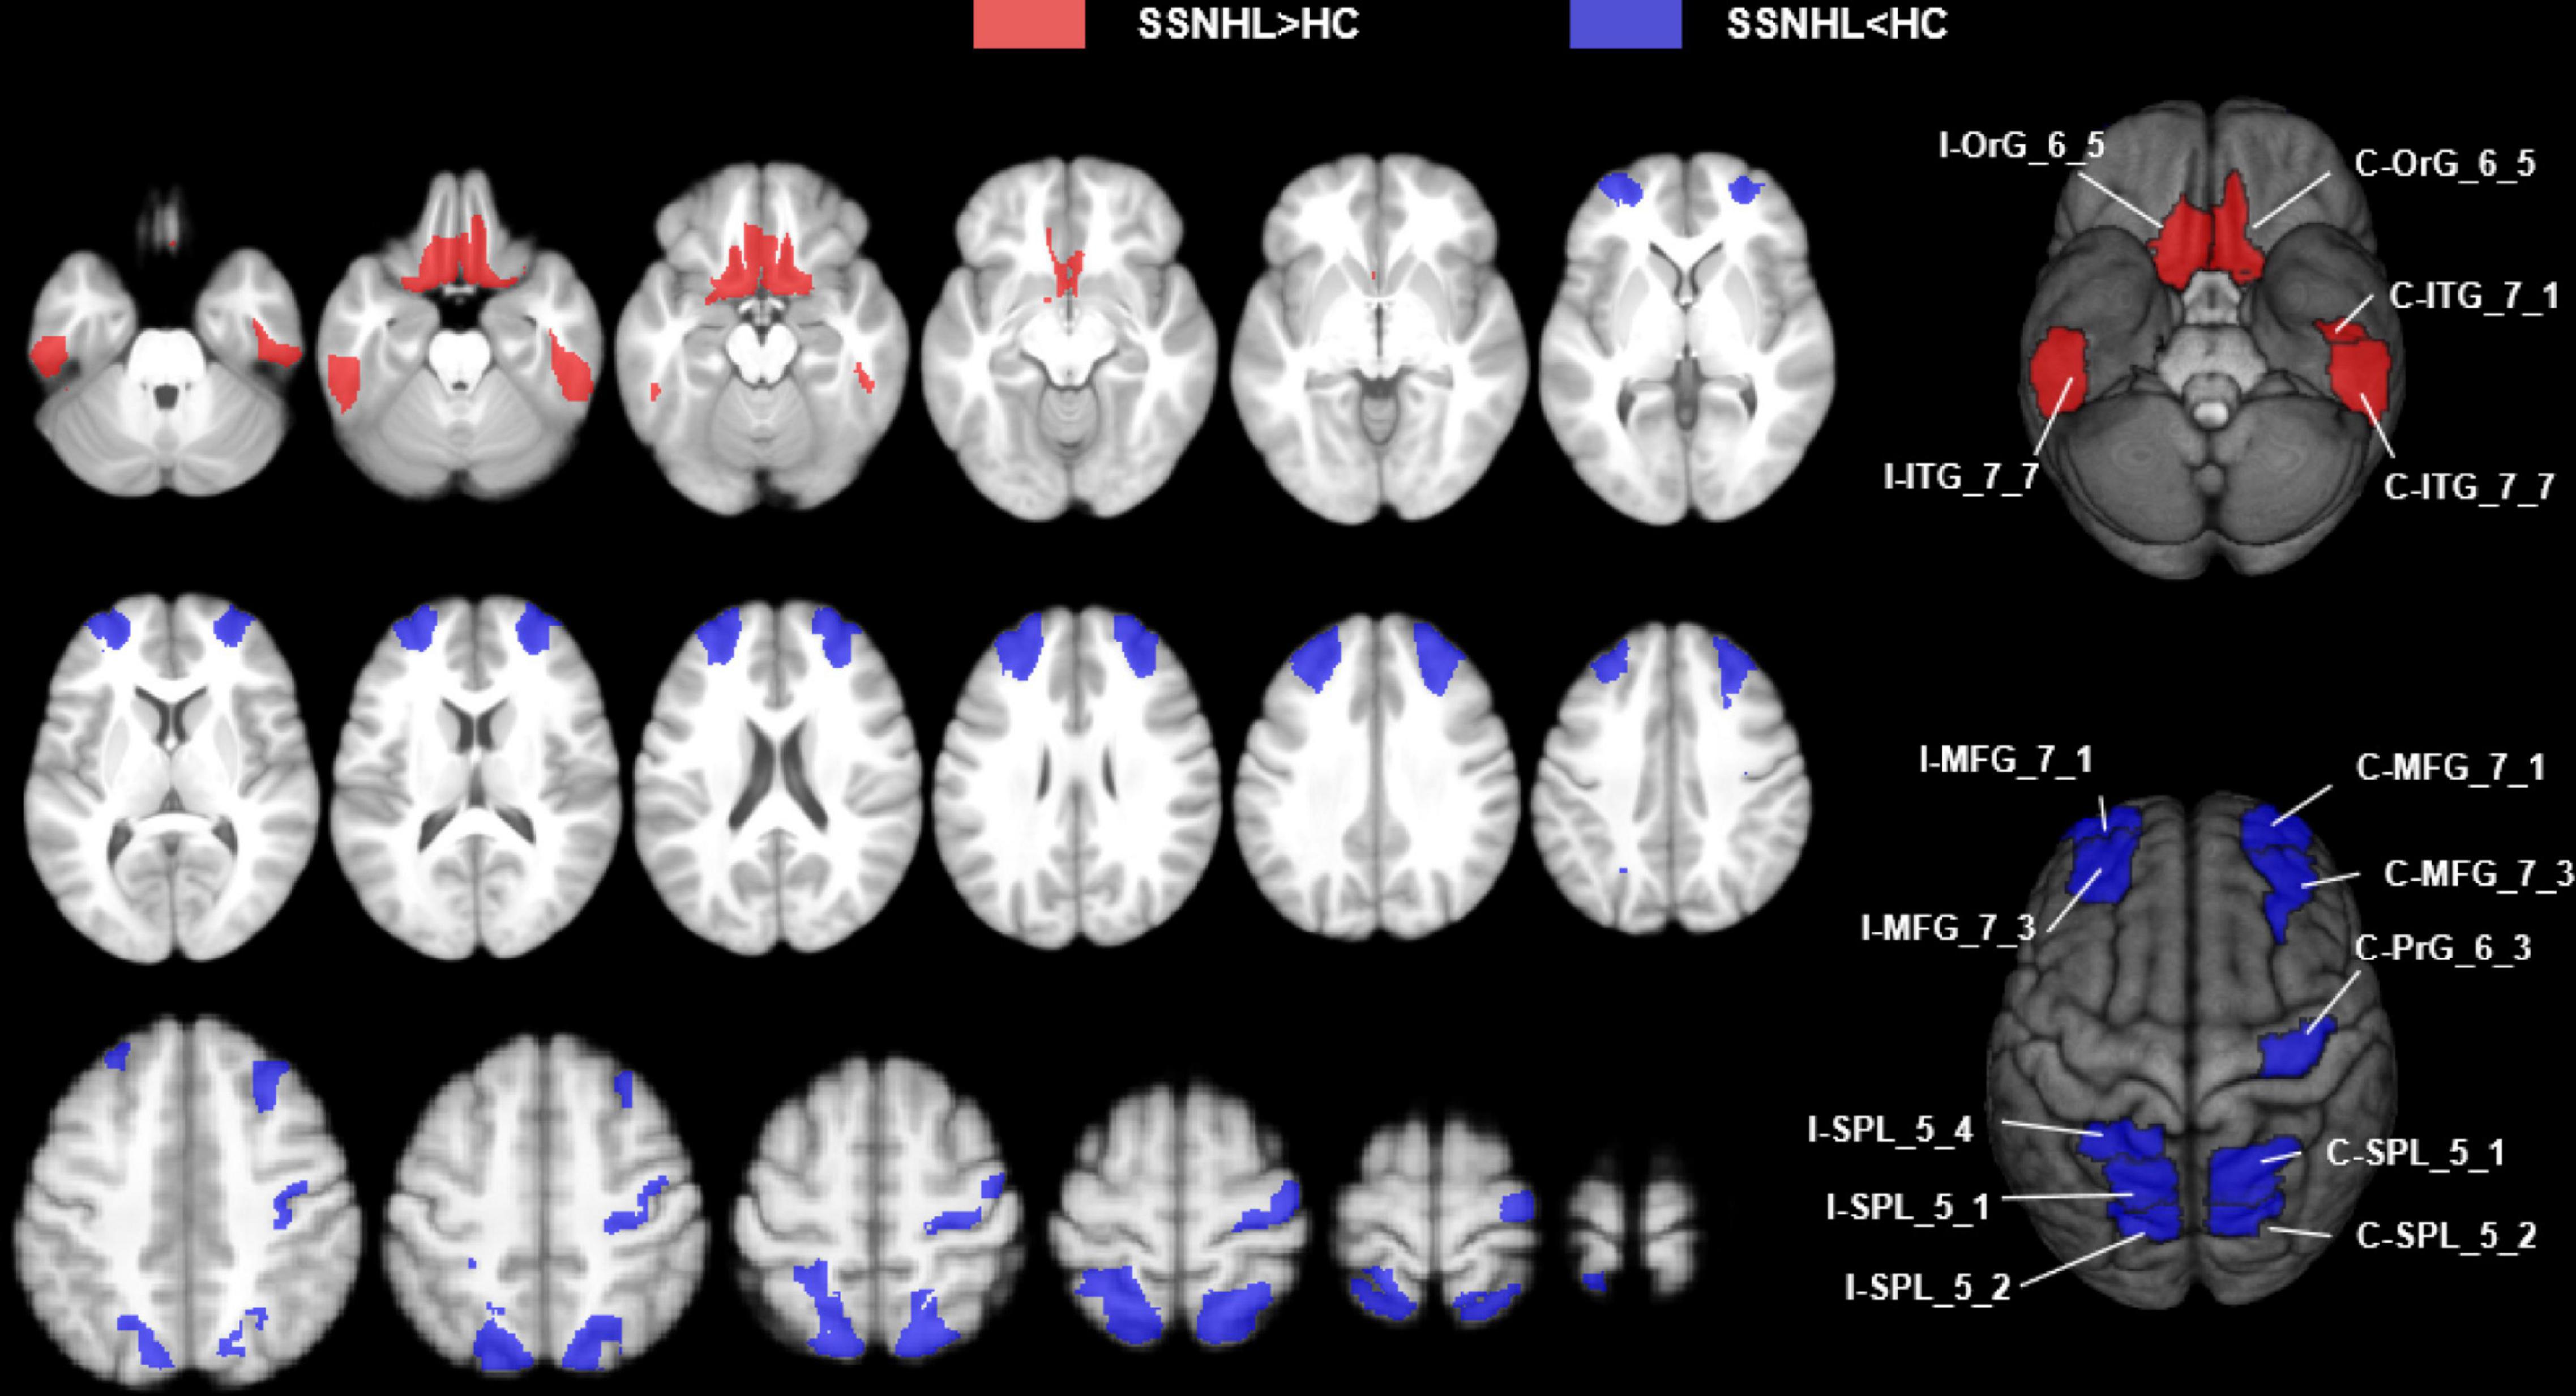

Results: The SSNHL patients exhibited decreased CBF in the bilateral middle frontal gyrus (MFG, MFG_7_1 and MFG_7_3), the contralateral precentral gyrus (PrG, PrG_6_3) and the bilateral superior parietal lobule (SPL, bilateral SPL_5_1, SPL_5_2, and ipsilateral SPL_5_4), p < 0.0002. Compared with HCs, unilateral SSNHL patients exhibited increased rCBF in the bilateral orbital gyrus (OrG, OrG_6_5), the bilateral inferior temporal gyrus (ITG, contralateral ITG_7_1 and bilateral ITG_7_7), p < 0.0002. lSSNHL showed abnormal CBF in left BA21 caudal (p = 0.02) and left BA37 dorsolateral (p = 0.047). We found that the CBF in ipsilateral MFG_7_1 of SSNHL patients was positively correlated with tinnitus Visual Analog Scale (VAS) score (r = 0.485, p = 0.008).

The SSNHL patients exhibited decreased rCBF in the bilateral middle frontal gyrus (MFG_7_1 and MFG_7_3), the contralateral precentral gyrus (PrG_6_3) and the bilateral Superior Parietal Lobule (bilateral SPL_5_1, SPL_5_2 and ipsilateral SPL_5_4), p < 0.0002 (Figures 4, 5A).

Figure 4. Abnormal CBF subregions in patients with unilateral SSNHL compared with healthy controls. Red, SSNHL (rCBF) > HC (rCBF); Blue, SSNHL (rCBF) < HC (rCBF). I, ipsilateral; C, contralateral; MFG, middle frontal gyrus; PrG, Precentral Gyrus; SPL, superior parietal gyrus; ITG, inferior temporal gyrus; OrG, orbital gyrus.

Figure 5. Comparisons of rCBF values between healthy controls and patients with SSNHL. (A) Decreased CBF subregions in patients with unilateral SSNHL compared with healthy controls. (B) Increased CBF subregions in patients with unilateral SSNHL compared with healthy controls. Data was mean ± SD. I, ipsilateral; C, contralateral; MFG, middle frontal gyrus; PrG, Precentral Gyrus; SPL, superior parietal gyrus; ITG, inferior temporal gyrus; OrG, orbital gyrus; SD, standard deviation.

Compared with healthy controls, unilateral SSNHL patients exhibited increased rCBF in the bilateral orbital gyrus (OrG_6_5), the bilateral inferior temporal gyrus (contralateral ITG_7_1 and bilateral ITG_7_7), p < 0.0002 (Figures 4, 5B).